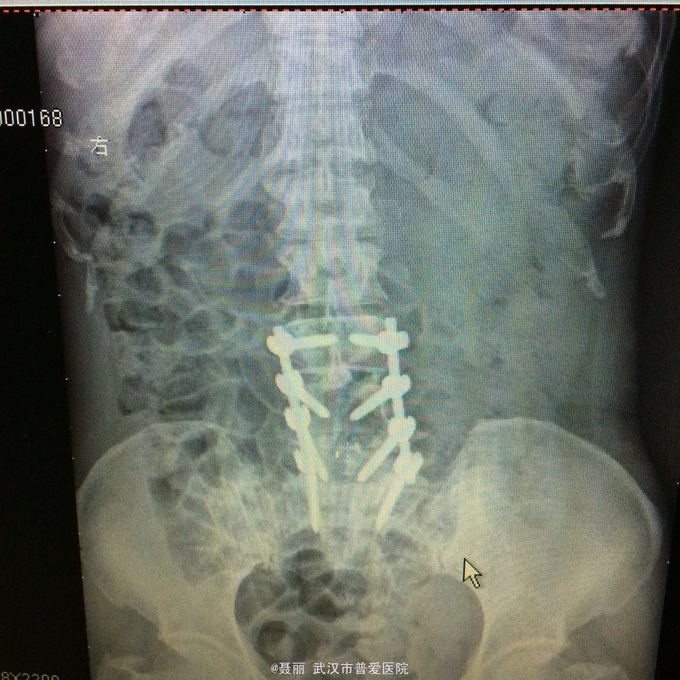

患者,女,51岁。 反复腰痛并间歇性跛行5年余,加重并左侧臀部2月余。 患者于5年前无明显诱因外伤诱因出现腰痛,不伴有双下肢麻木、乏力及间歇性跛行,卧床休息后好转,间歇发作,进行性加重。 既往史:有高血压病、糖尿病病史,否认有药物过敏

:L4/5棘突间轻压痛,叩痛,棘间左侧椎旁压痛;双下肢肌力、肌张力正常,病理反射未引出。 门诊资料:外院行腰椎CT检查示:L3-S1椎间盘膨出,L4椎弓崩裂并向前滑脱(重度)椎管狭窄。 入

入院诊断:、腰椎滑脱(L4/5 峡部裂性) 诊疗计划:1:完善有关检查2卧床休息,行改善微循环、3.腰椎后路复位减压植骨融合术

行改善微循环、3.腰椎后路复位减压植骨融合术 腰椎滑脱(L4/5 Ⅱ度)、腰椎管狭窄症(L3/4)、腰椎间盘突出症(L5/S1)查体双下肢感觉、活动无明显异常。双下肢末梢血液循环可。换药见伤口对合良好,无明显红肿渗出。伤口已拆线。嘱加强双下肢活动及功能锻炼,避免下肢深静脉血栓,主动及被动四肢活动,预防血静脉及床褥形成,加强腰背肌锻炼,适量康复功能锻炼。一个月后来复查伤口愈合好,疼痛没有,活动可